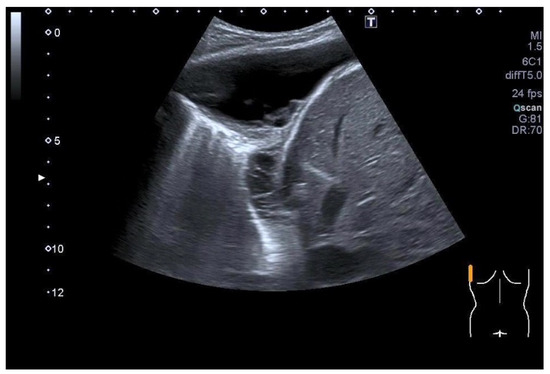

| Tuberculous pleuritis | Pleura effusion with fibrin strands, pleural calcification, and thickening. Hypoechoic granulomatous inflammation and granulomas with hyper-enhancement on CEUS in thickened pleura. Hypoechoic caseous abscesses in thickened pleura, hypo- or nonenhanced, heterogeneously enhanced lesions, with contrast-enhanced septations and contrast-enhanced rim. |